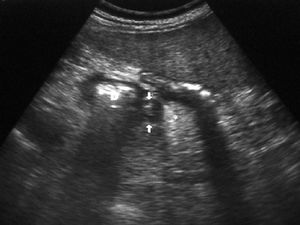

La forma más frecuente es la ausencia de rotación intestinal, que implica importantes alteraciones anatómicas valorables tanto en la ecografía como por la TC. Los principales hallazgos radiológicos son: alteración en la posición del duodeno, que no pasa entre la aorta y la arteria mesentérica superior (AMS); la localización en el hemiabdomen derecho de las asas de intestino delgado y en hemiabdomen izquierdo las de intestino grueso, y una verticalización o inversión de los vasos mesentéricos respecto a su posición normal, quedando la AMS a la derecha y la vena mesentérica superior (VMS) a la izquierda1,2 (fig. 1).

Fig. 1--Malrotación intestinal. (A) y (B) Tomografía computarizada con contraste oral e intevenoso mostrando inversión de la arteria mesentérica superior (AMS) (punta de flecha) y la vena mesentérica superior (flecha). La tercera porción duodenal (D) no cruza la línea media entre la aorta y la AMS, localizándose las asas de yeyuno a la derecha.